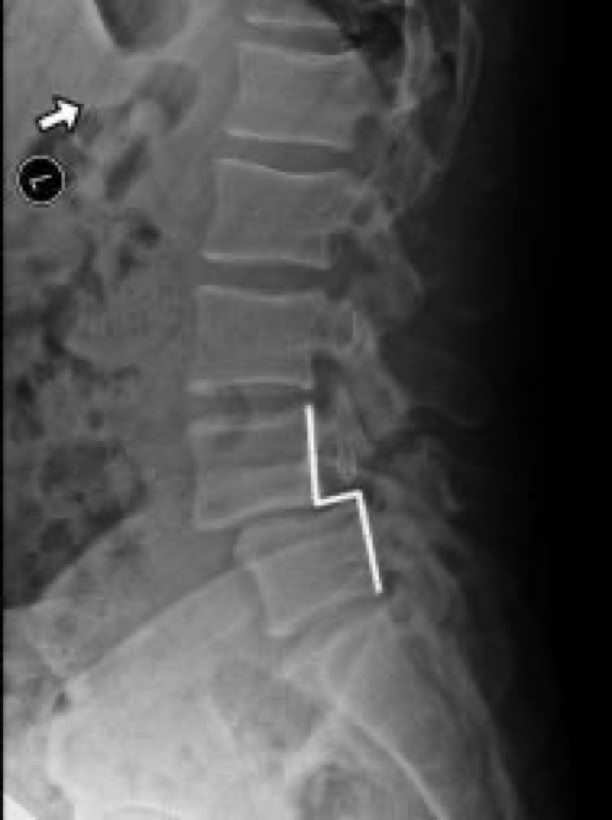

Spondylolisthesis is most commonly observed in the lumbar spine, which bears the majority of the body’s weight. To evaluate spinal instability, X-rays are typically taken while the patient bends forward (flexion) and backward (extension). Under normal conditions, there should be no significant motion at the affected level. However, increased movement between the flexion and extension X-rays often correlates with more pronounced symptoms, indicating a greater degree of instability and discomfort for the patient.

fracture of the pars defect

anterior slippage of vertebra

X-RAY SHOWING A PARS FRACTURE DEFECT

THE WHITE OUTLINE SHOWS THE SLIPPAGE.